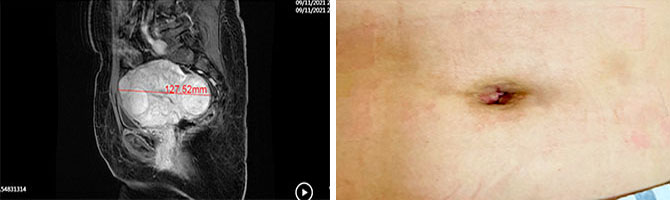

2020年12月,借鉴韩国妇科腔镜肿瘤专家Kim Sang Wun的经验,我院妇科李志刚主任团队开始大力开展经脐单孔腹腔镜手术,至今,已成功实施近150例,技术日臻成熟,取得良好的近期、远期预后效果,已成为妇科特色手术之一。其中全宫切除术占63%。在这些病例中,有236*156*140mm卵巢巨大肿物的病例,也有子宫大小达127*100*90mm、重量达到800余克的特殊病例,均通过单孔腹腔镜顺利完成操作。

切除巨大子宫肌瘤后,切口瘢痕隐形于脐部

妇科团队的脐部切口不同于国内常用切口,长度仅1.8-2cm,于脐部切口置入单孔多通道设备,再置入手术器械完成手术操作,可经脐部直接取出标本,而切除子宫则从阴道取出。缝合后主要利用脐部皱襞遮挡切口,脐部瘢痕较隐匿,最大程度达到美容的效果。且术后脐部伤口,无特殊并发症,颇受患者欢迎。